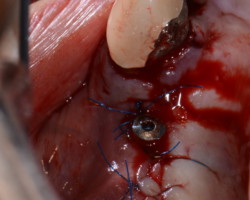

- Phase correctrice : créer des conditions compatibles avec la maintenance. (chirurgie résectrice, implantoplastie, correction prothétique)

- Phase réparatrice: Réduire la profondeur de poche et réparer les tissus détruits.

- Phase de maintenance